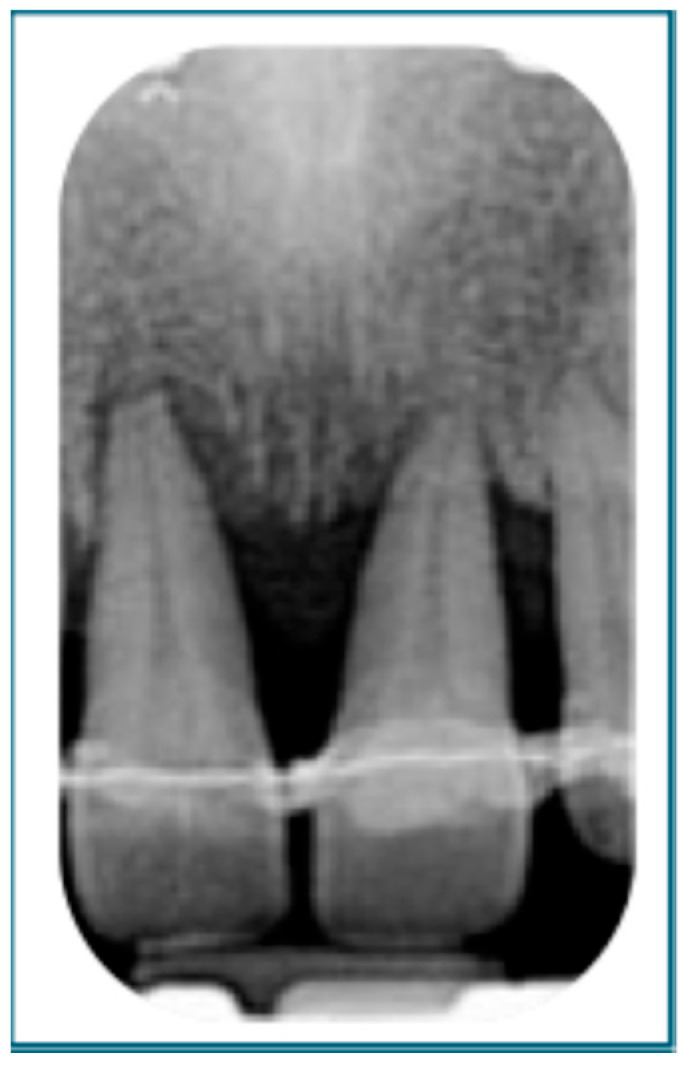

Abstract Image